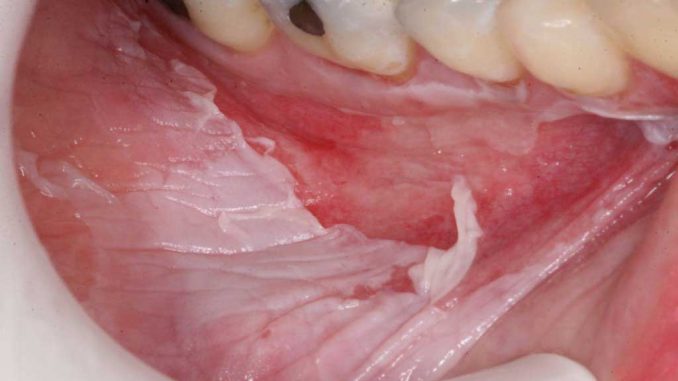

Ожог слизистой оболочки

Состояние возникает вследствие воздействия на слизистую спиртом, мышьяком, высокими температурами, агрессивными химическими средствами, слишком горячей пищей или напитками. В результате наблюдаются симптомы:

- появление волдырей, изъязвлений;

- Самой тяжелой, опасной формой травмы является третья стадия, или некроз. При этом усиливаются симптомы первых двух стадий, волдыри полностью покрывают слизистую, преобразуются в болящие язвы. При этом отмирают мягкие ткани, чернеют десны.

Через некоторое время обожженная область становится шершавой, на деснах возникают разного диаметра лопающиеся пузыри, которые превращаются в открытые глубокие раны. Весь процесс сопровождается постоянными болезненными ощущениями, усиливающимися при соприкосновении поверхности с пищей, водой.

Если лечение не начато своевременно, происходит отек, потемнение десны, кровоточивость, некроз.

Симптомы химического воздействия на десны:

- отек и почернение тканей;

- волдыри (не всегда).

Основные симптомы при химическом ожоге поверхности десны немного отличаются от термического. При этой форме у больного могут отсутствовать объемные волдыри, рана уходит вглубь и окружена опухшими тканями. При этом беспокоит жуткая боль, зуд внутри и другие неприятные симптомы.